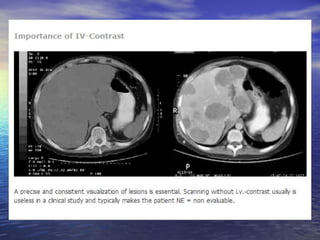

Diferença da avaliação em relação à fase do contraste

fase arterial                           Fase portal